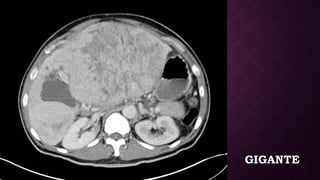

GIGANTEGIGANTE

TOMOGRAFÍATOMOGRAFÍA • Por logeneral, la masa capta contraste intensamente durante la fase arterial tardía (~ 35 segundos) y luego se elimina rápidamente, llegando a ser indistinta o hipoatenuante en la fase venosa portal, en comparación con el resto del hígado. • Además, pueden estar asociados con una anomalía de perfusión en forma de cuña debido a shunts arterioportales, y esto, a su vez, puede resultar en un cambio graso focal en el hígado normal.  • También puede observarse un halo graso focal alrededor de un HCC en un hígado graso. • El trombo tumoral de la vena portal puede distinguirse de un trombo blando al demostrar mejoras.